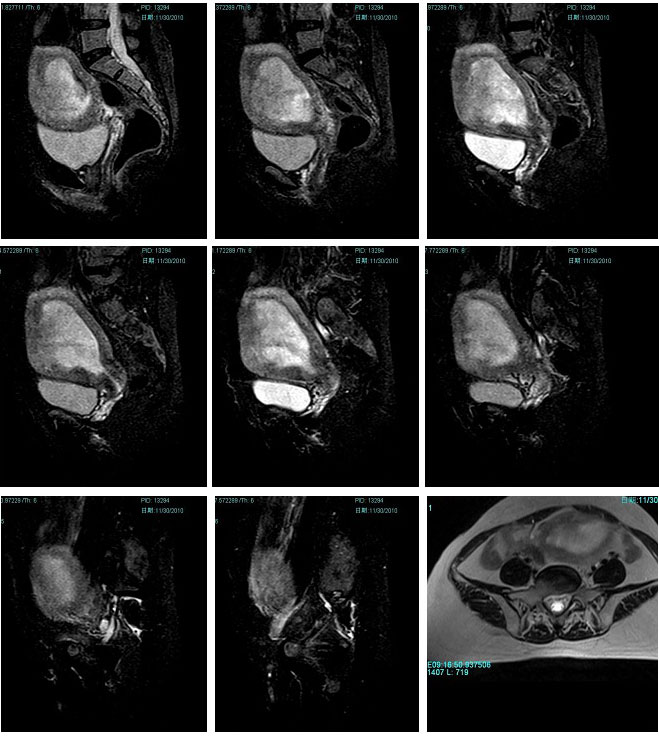

子宫恶性中胚叶混合瘤(癌肉瘤)

女性患者,52岁,月经量大,间断下腹痛一年余。多考虑:1:子宫前壁肌瘤。2:子宫内膜癌可能性大。已取活检,病理结果过几天出来。各位高手先讨论讨论。

子宫内膜太厚,结合带不完整,考虑内膜癌,建议刮宫病检。

宫内膜太厚,结合带不完整,考虑内膜癌,建议刮宫病检。

子宫内膜太厚,结合带不完整,考虑内膜癌,建议刮宫病检。支持!